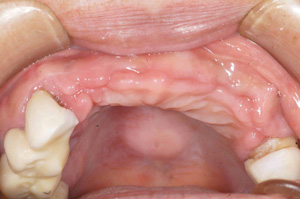

@@R.S‚³‚ñ@56Î —«  ‘åŠw‹³Žö @Žèp“ú@‚Q‚O‚O‚W”N ‚QŒŽ ‚X“úi“yj@㉺Š{  ƒm[ƒxƒ‹ƒKƒCƒhŽg—p@Ö¬“à’ÁÖ@•¹—p@@@

@@@@@ãŠ{  All on ‚U@‘¦Žž‰Ád@@

@@@@@@@@@@@@@ Rpl Tapered Rp  ‚P‚O mm(‚U–{)

@@@@@‰ºŠ{¶‰E@‘¦Žž‰Ád@ ‚R Unit Bridge@

@@@@@@@@@@@ @Rpl Tapered Rp  ‚P‚O mm(‚S–{)@@–ƒWƒ‹ƒRƒjƒAƒNƒ‰ƒEƒ“‚ÅÅI•â’Ô